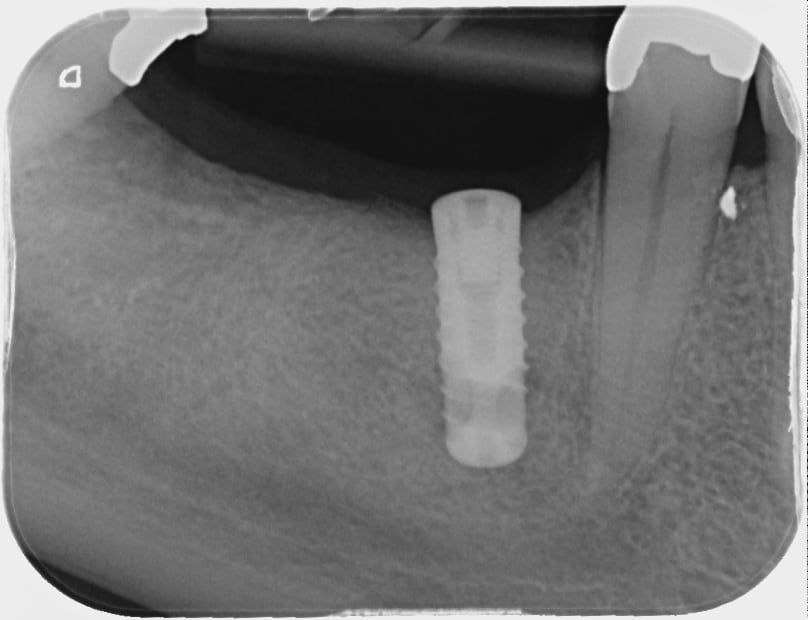

j'ai un patient qui se présente avec un implant en bouche posé il y plus d'une dizaine d'années dans un cabinet qui a disparu depuis.

il ne s'est jamais fait poser la couronne.

Je n'arrive pas à trouver de quel implant il s'agit...

Si quelqu'un le reconnaît, ça m'éviterait de le déposer.

Faudrait une retroalveolaire mais ça peut évoquer un screw vent de zimmer

https://www.spotimplant.com/fr/implants-dentaire/zimmer/screw-vent

un Zimmer.....non, je n'y parie même pas un centime....

par contre un bis biotech.....

https://osseosource.com/bis-3-9-/p-1055.html

à vérifier avec une rétro....

merci de vos réponses, voici une rétroalvéolaire. Je me suis aussi dit que c'était un zimmer screw vent d'ancienne génération, posé au début des années 2000.